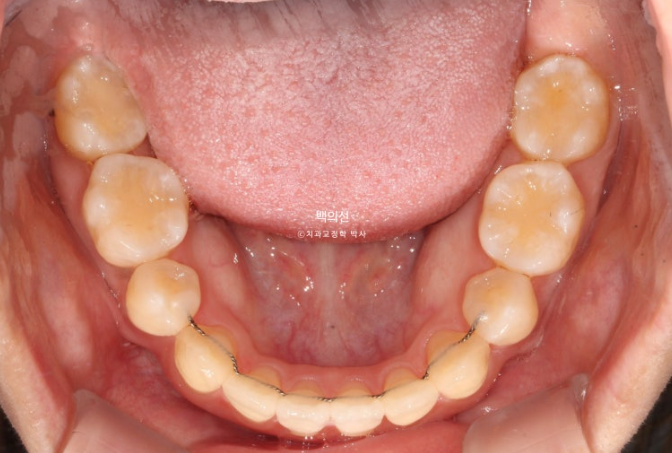

아래에도 첫번째 작은어금니가 양쪽에 각각 결손되어 있네요. 그래서 공간들이 남아 치아들이 벌어져 있습니다.

태어날때부터 없는 치아를 선천적 결손치라고 합니다.

결론적으로 작은어금니 4개 중 3개가 입안에서 안 보이는 상태입니다. 2개는 결손, 한 개는 매복.

마침 돌출입도 보여서 이런 경우 유일하게 남아있는 작은어금니 1개만 빼면 작은어금니 4개 발치교정 한셈 치고 교정치료를 하면 좋습니다.

유일하게 잘 나와있는 작은어금니 1개를 아쉽지만 발치하고 인비절라인 치료에 들어갔습니다.